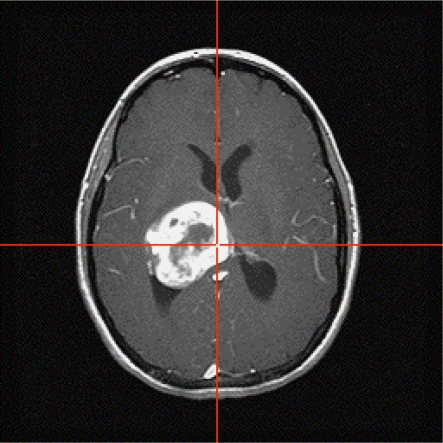

Figure 5a:

(a) Contrast-enhanced anatomic image from patient 4. (b–e) MR signal– and concentration-time curves demonstrating confounding T1 and T2 leakage and/or residual susceptibility effects. Data in b and c were collected with acquisition method A (GRE echo-planar imaging with 90° flip angle during primary injection of standard dose of contrast agent). Data acquired during primary injection demonstrate strong T1 leakage effect, as evidenced by the fact that postbolus signal continues rising above its prebolus baseline on b, which corresponds to postbolus portion of ΔR2*(t) decreasing below its prebolus baseline level on c. Data on d and e are same types of curves, taken from same voxel, but were acquired with acquisition method D (GRE echo-planar imaging with 90° flip angle during secondary injection of double dose of contrast agent after preload administration). Postbolus signal remains below its prebolus baseline level on d, which corresponds to elevated postbolus portion of ΔR2*(t) on e. This is consistent with a dipolar T2 leakage effect or a residual susceptibility leakage effect. a.u. = Arbitrary units.